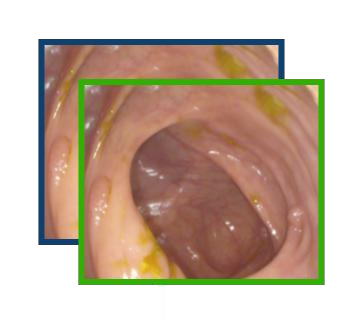

Early detection, accurate segmentation, classification and tracking of polyps during colonoscopy are critical for preventing colorectal cancer. Many existing deep-learning-based methods for analyzing colonoscopic videos either require task-specific fine-tuning, lack tracking capabilities, or rely on domain-specific pre-training. In this paper, we introduce \textit{PolypSegTrack}, a novel foundation model that jointly addresses polyp detection, segmentation, classification and unsupervised tracking in colonoscopic videos. Our approach leverages a novel conditional mask loss, enabling flexible training across datasets with either pixel-level segmentation masks or bounding box annotations, allowing us to bypass task-specific fine-tuning. Our unsupervised tracking module reliably associates polyp instances across frames using object queries, without relying on any heuristics. We leverage a robust vision foundation model backbone that is pre-trained unsupervisedly on natural images, thereby removing the need for domain-specific pre-training. Extensive experiments on multiple polyp benchmarks demonstrate that our method significantly outperforms existing state-of-the-art approaches in detection, segmentation, classification, and tracking.